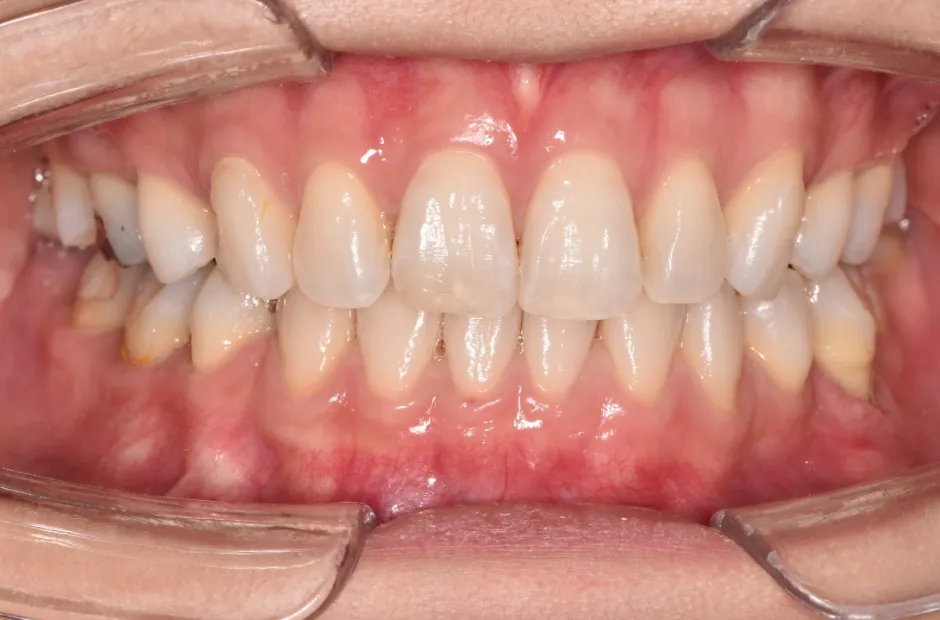

治療前